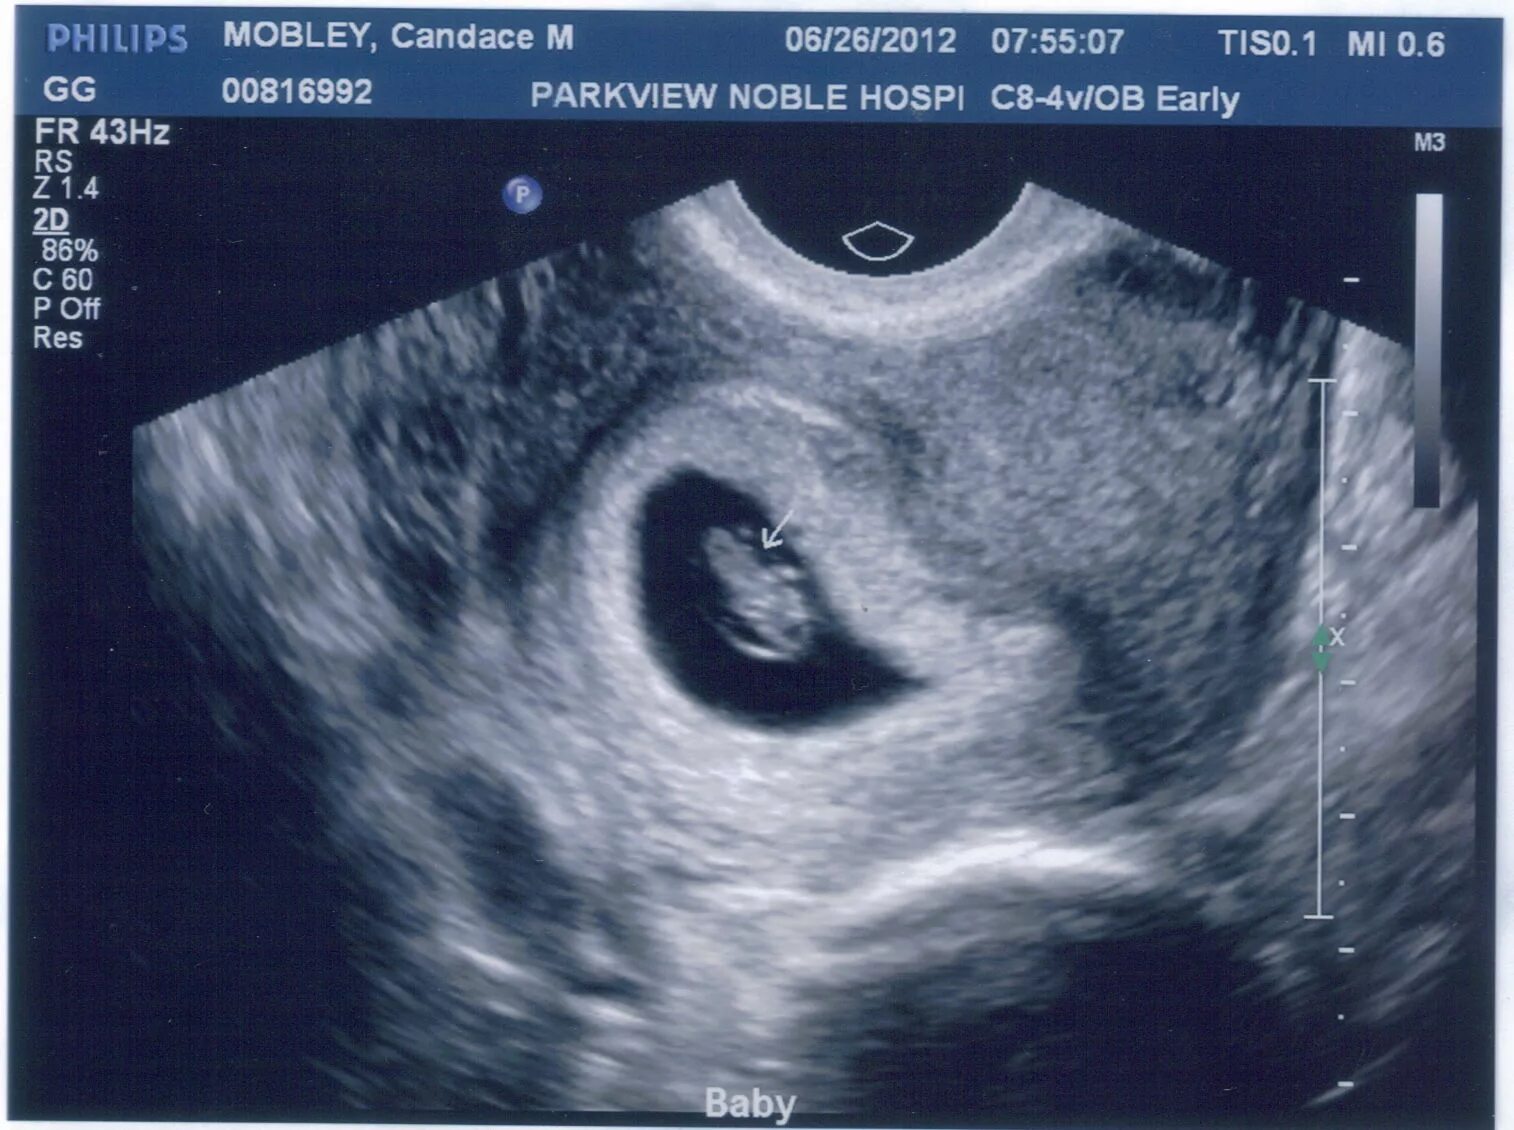

Через 4 6 недель после